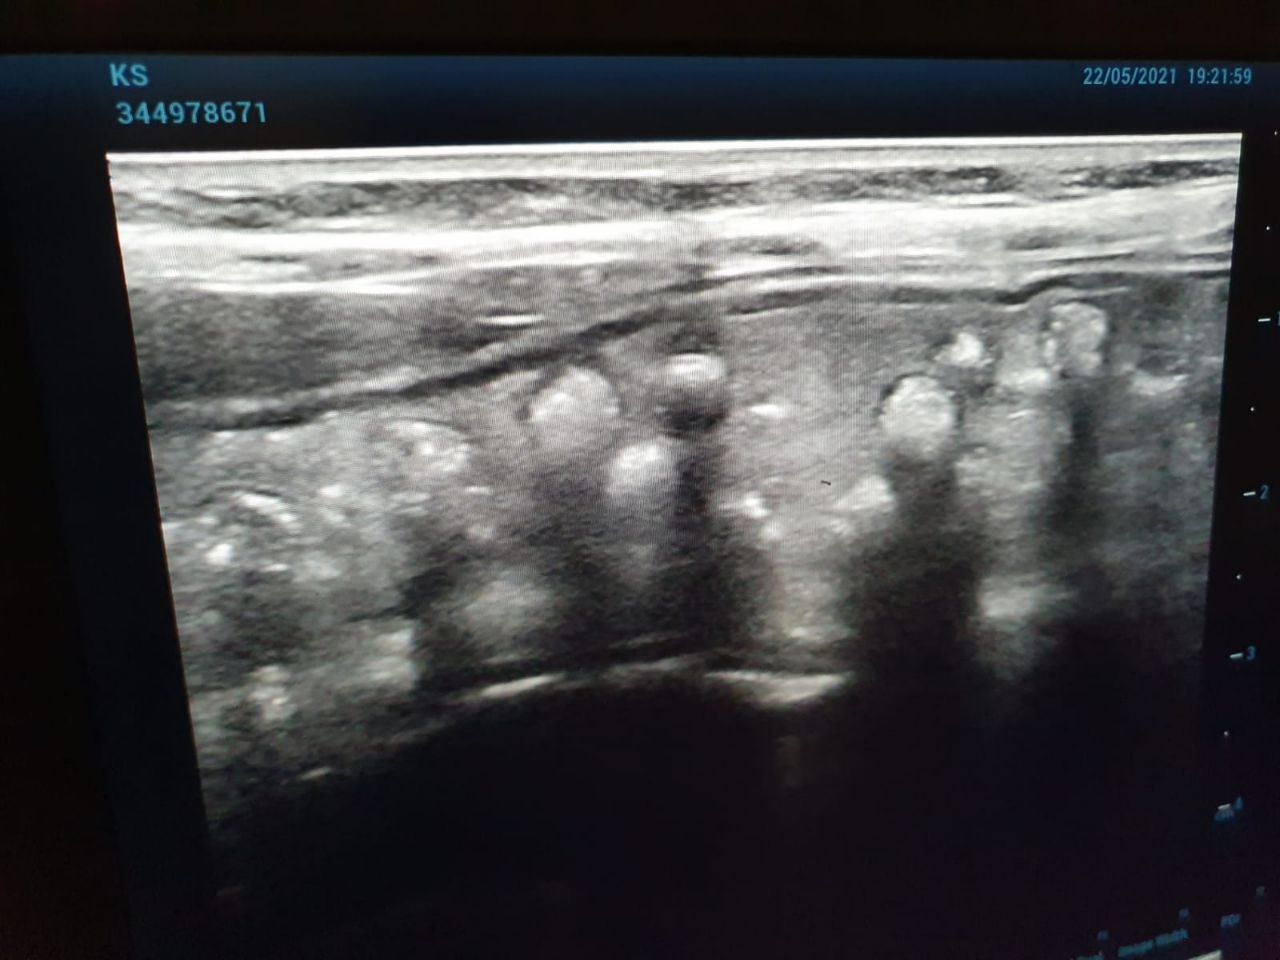

בצילום האולטראסאונד שנערך לפעוט זוהתה כמות גדולה של כדורים בקיבה, חלקם כבר התקדמו למעי הדק.

לאחר התייעצות בין הרופאים, הוחלט להעביר את הפעוט לחדר הניתוח, שם גילו כי מדובר בכדורי ג'לי קטנים למשחק בקוטר של 3-4 מ"מ.